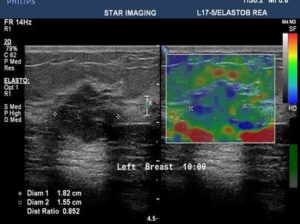

39yr old lady with history of lump in the left breast UIQ, No previous imaging done. No positive family history for CA Breast/Ovary. Pre-Menopausal Status.

Mammography- Fairly well circumscribed predominantly sold lesion in the left breast UIQ with partially obscured margins. No spiculations. No associated microcalcifications noted. Sonography: Well defined hypoechoiec lesion with smooth margins.

Low-grade Mucinous Carcinoma ER?PR- +ve HER-2 NEU -VE